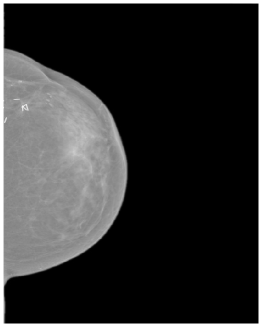

As data augmentation, random Gaussian noise (μ=0\mu=0, σ=0.005\sigma=0.005), random horizontal flipping (p=0.5p=0.5), random rotation (15-15^{\circ}, +15+15^{\circ}), random translation (0, 0.1), random shearing (25-25^{\circ}, +25+25^{\circ}), scaling by a random factor between 0.8 and 1.6 were used. Three standardized mammography images from different datasets are shown in the Figure 6.

Refer to caption

(a) Hacettepe

(b) VinDr

(c) CSAW

Figure 6: Standardized mammography samples from Hacettepe, VinDr, and CSAW dataset.